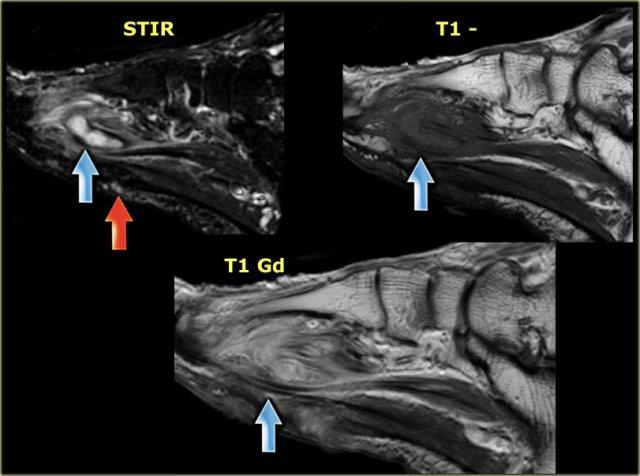

Đây là hình ảnh của một bệnh nhân có khuyết hổng da nhỏ và phù nề dưới da ở vùng xương bàn chân.

Một dấu hiệu thứ phát là áp xe được ghi nhận ở vùng bàn chân trước, với tín hiệu cao trên chuỗi xung STIR, tín hiệu thấp hoặc trung gian trên chuỗi xung T1W, và bắt thuốc dạng viền với tín hiệu cao trên chuỗi xung T1+Gd.